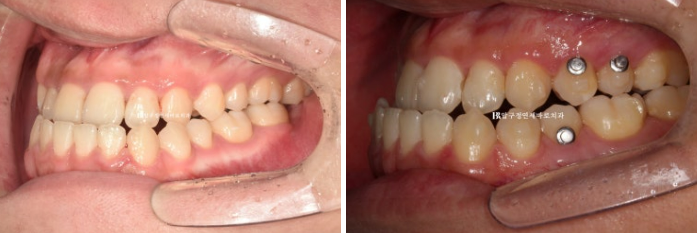

다음 사진은 구강악면외과에서 양악수술을 마친 뒤 한달간의 회복기를 가진 후 내원 시 모습입니다.

24.02

교합이 매우 좋습니다.

술전 교정도 워낙 잘 되고 구강악면외과 원장님도 수술을 잘 해주셔서

사실 술후교정으로는 별로 할 것이 없었습니다.

그래도 중심선과 좀 더 긴밀한 교합을 위해서 추가장치 제작을 합니다.

추가장치로 술후교정을 3개월부터 8월까지 약 5개월 진행했고 드디어 치료를 마무리 했습니다